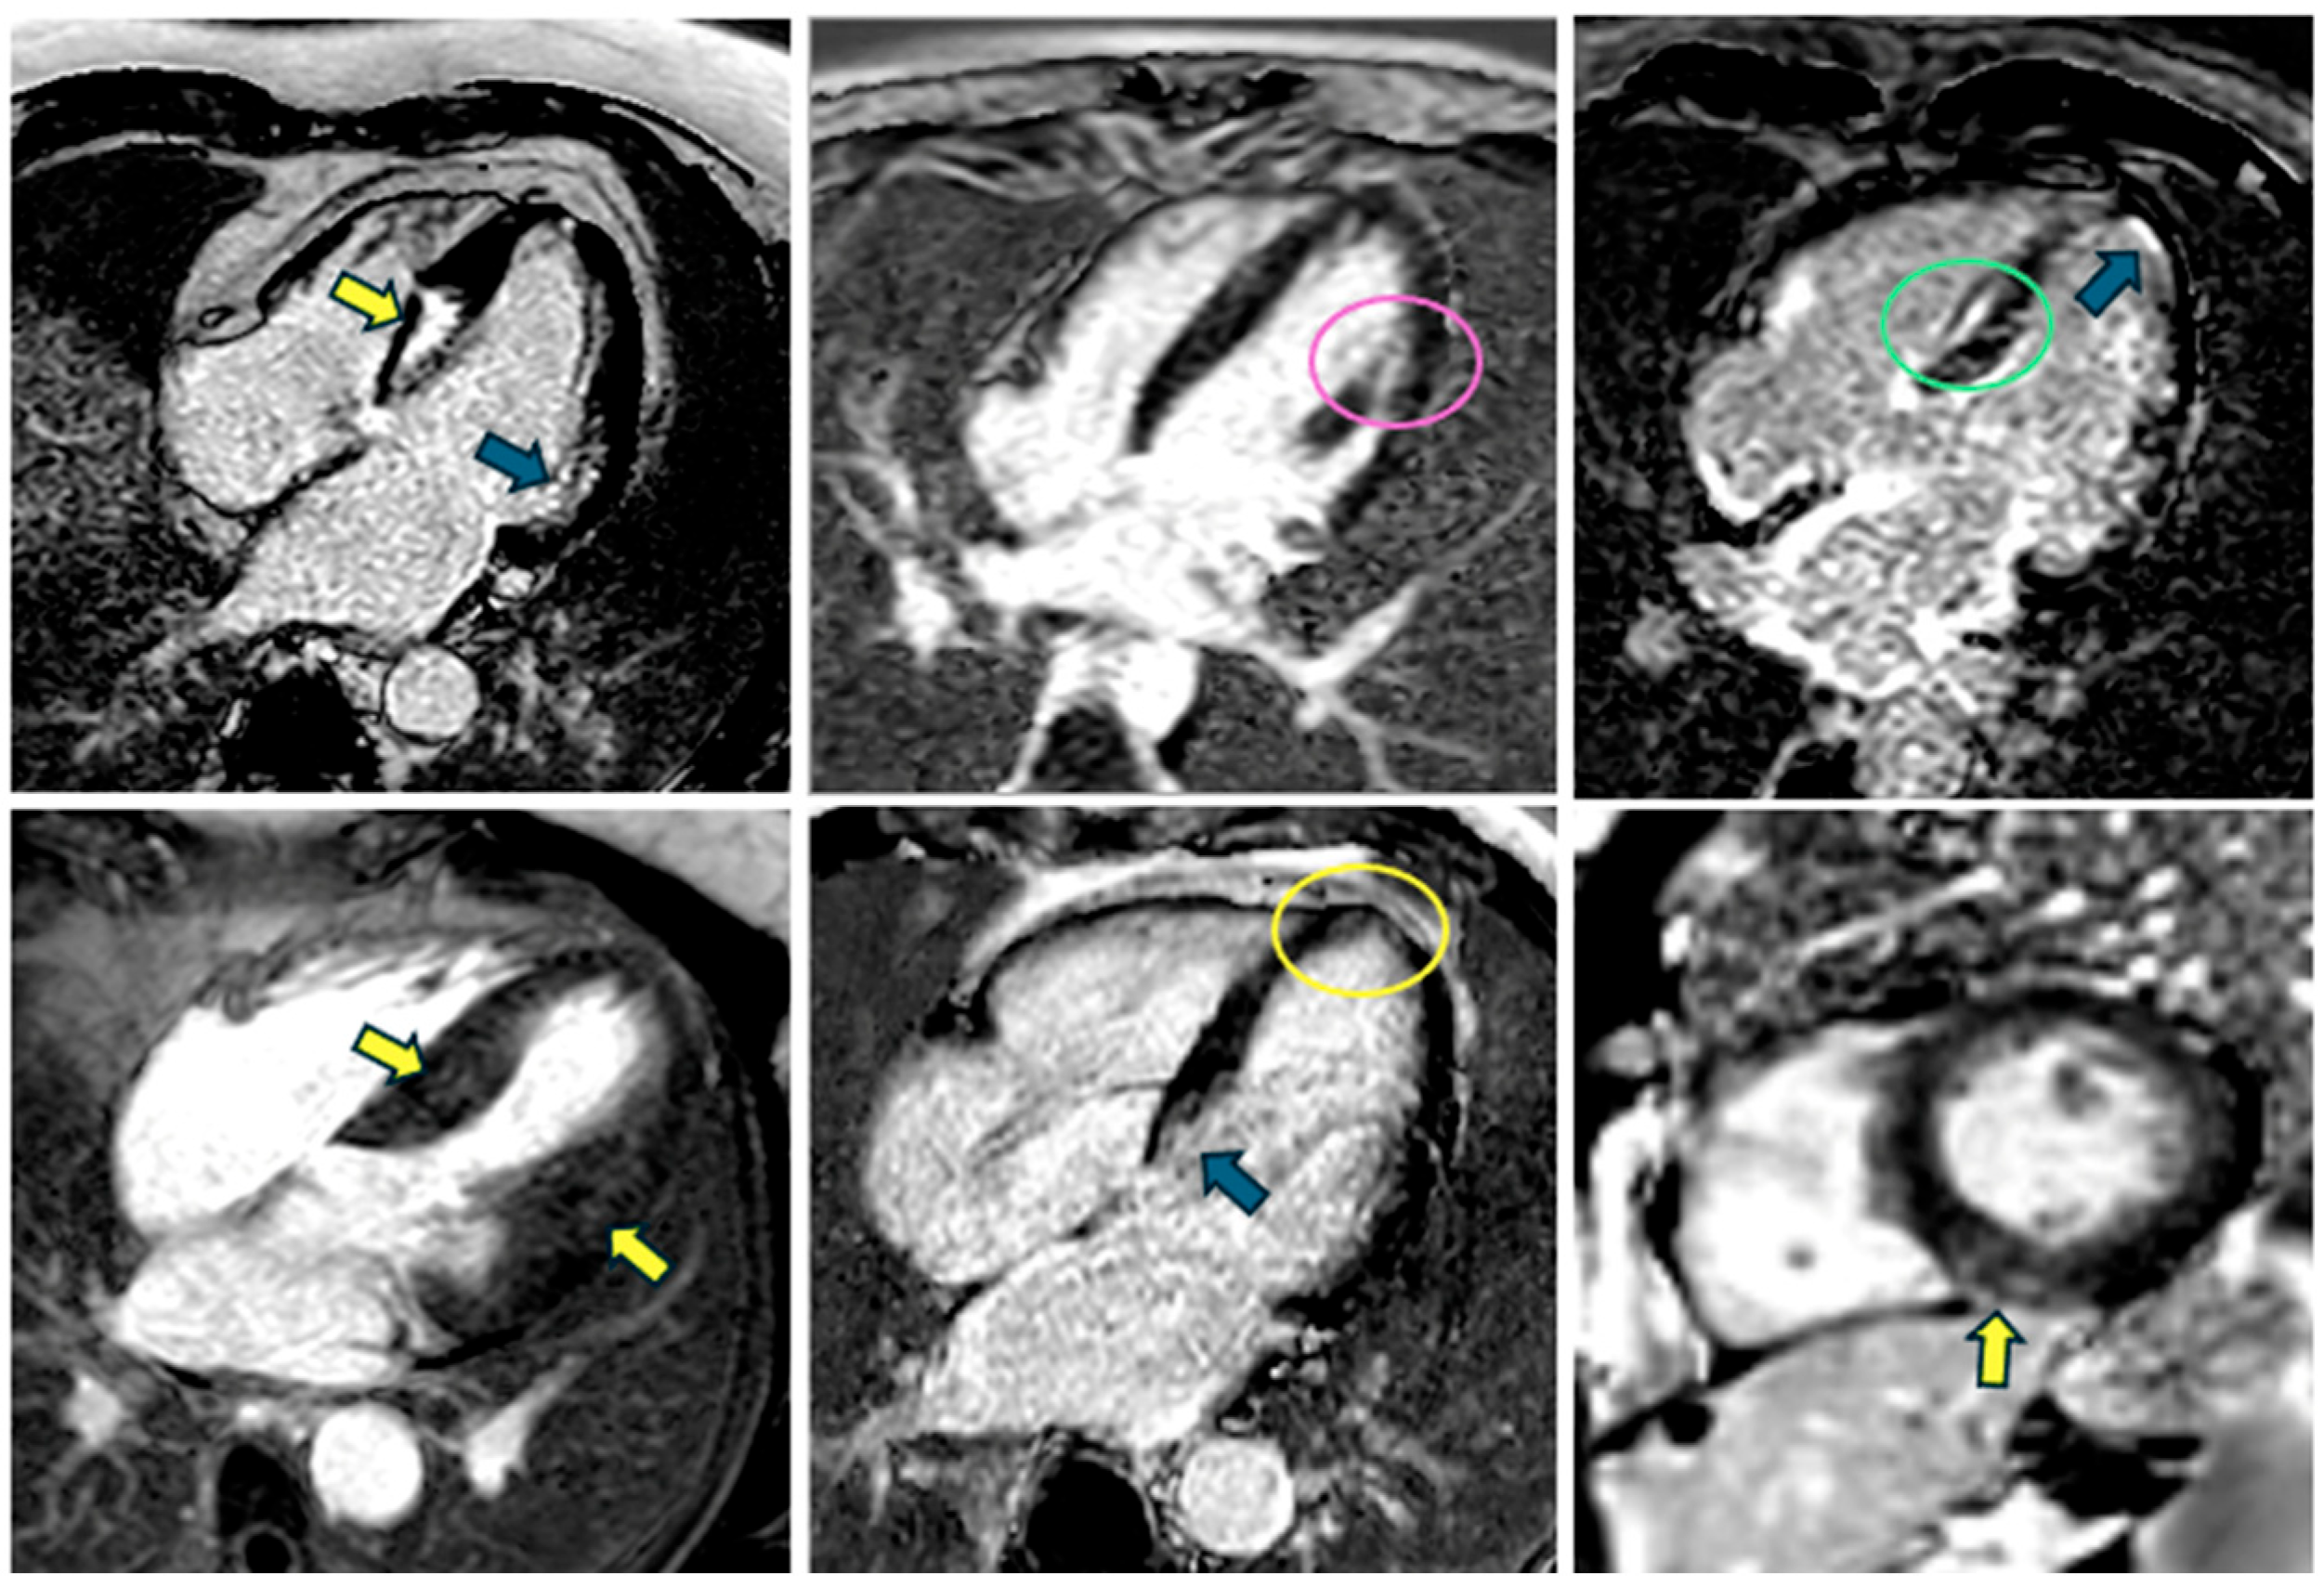

5.3. Late Gadolinium Enhancement

5.4. Perfusion